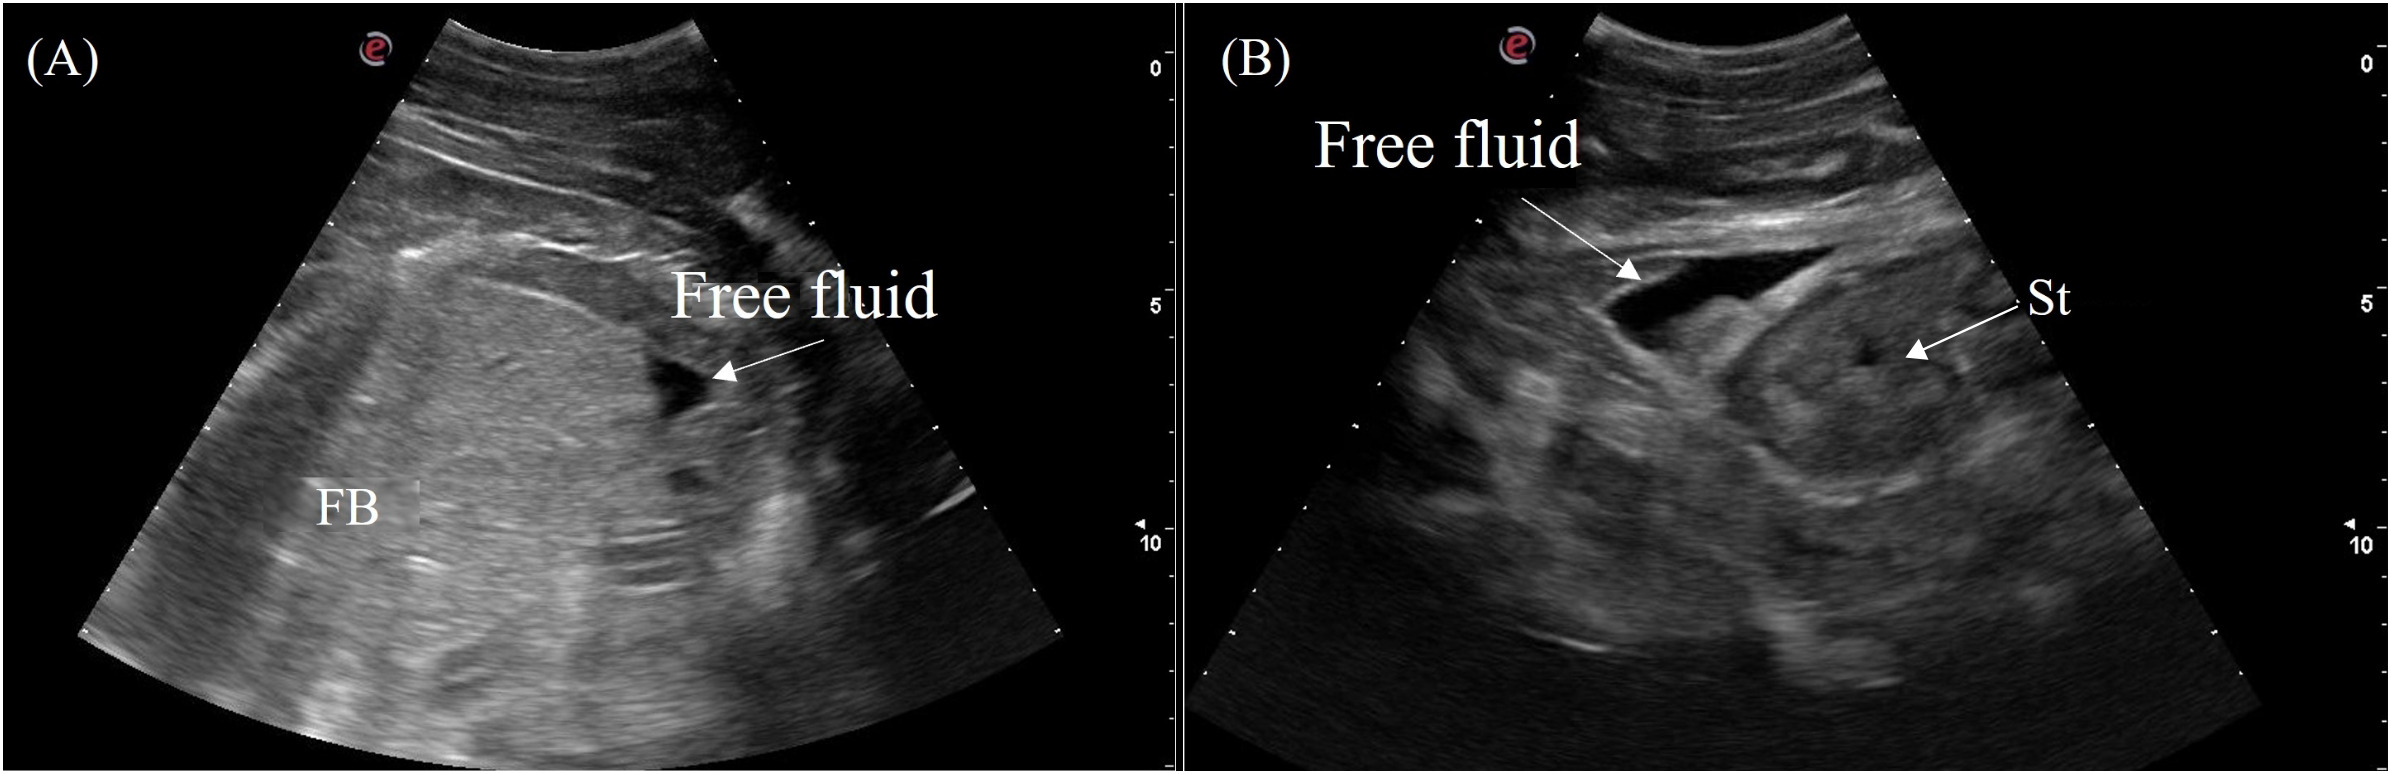

3.3.10 Coelomic cavity

A small to moderate amount of free anechoic fluid was detected in the male false gharial adjacent to the stomach and caudal to the fat body (Figure 15). Otherwise, no coelomic fluid was grossly detected in all other animals.

Figure 15

Ultrasonographic appearance of free fluid (A) caudal to the fat body and (B) adjacent to the stomach in a male Tomistoma schlegelii. [FB, fat body; FF, free fluid; St, stomach].